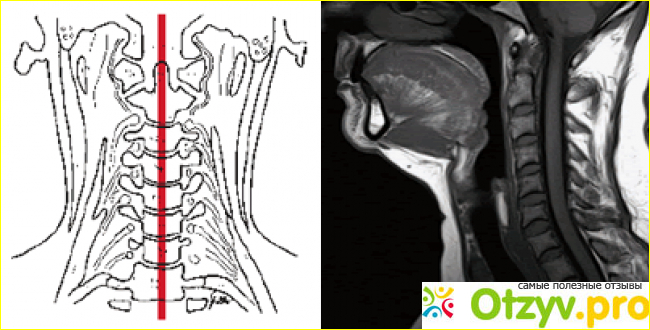

Гипоплазия – это недоразвитие тканей или органов организма человека. Это тяжелое нарушение влияет на кровоснабжение внутри черепа человека и может быть получено при рождении ребенка или приобретено в процессе жизни как у женщин и мужчин. Чаще всего встречается гипоплазия правой позвоночной артерии, реже — левой и очень редко двусторонняя гипоплазия позвоночных артерий.

Диагностика в этом случае начинается с анализа анамнестических сведений и назначения дополнительных исследований, таких как УЗИ позвоночных артерий и других.